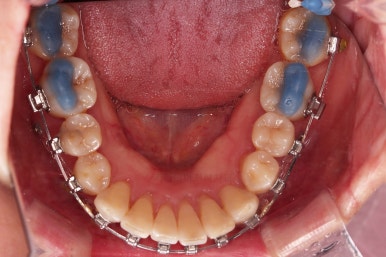

마무리 사진이에요.

치열이 매우 가지런해졌고, 틈도 없고, 앞니의 뻗친 느낌도 사라졌네요.

교합도 좋고요.

삐뚤고 솟구쳐 있던 치열도 가지런하게 되었고, 틈새도 다물어졌으며 뻗쳐 있던 느낌도 개선이 되었어요.

18개월의 기간동안 부산성인교정 많은 점들이 개선되 만족스러운 치료결과였어요.

이상 미니스크류를 이용한 비발치 치주교정, 부산성인교정, 중년교정 치료사례였습니다.